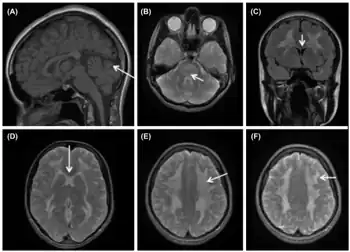

a) Cerebellar vermis atrophy and normal gyral pattern b)hyperintensities in the dorsal pons and mesencephalon c,d)signal abnormalities in the cerebral white matter e,f)white matter involvement with sparing of the U-fibers

While the disease manifests early in life in most cases, diagnosis of the disease is often quite delayed.[1][3][4] The symptoms that affected patients present vary, but the most common presenting symptoms are gastrointestinal issues such as nausea, vomiting, abdominal pain, and diarrhea, and neurologic or ocular symptoms such as hearing loss, weakness, and peripheral neuropathy.[3] These gastrointestinal symptoms cause patients with MNGIE to be very thin and experience persistent weight loss and this often leads to MNGIE being misdiagnosed as an eating disorder.[1] These symptoms without presentation of disordered eating and warped body image warrant further investigation into the possibility of MNGIE as a diagnosis.[1] Presentation of these symptoms and lack of disordered eating are not enough for a diagnosis. Radiologic studies showing hypoperistalsis, large atonic stomach, dilated duodenum, diverticula, and white matter changes are required to confirm the diagnosis.[3] Elevated blood and urine nucleoside levels are also indicative of MNGIE syndrome.[1] Abnormal nerve conduction as well as analysis of mitochondria from liver, intestines, muscle, and nerve tissue can also be used to support the diagnosis.[1][3]